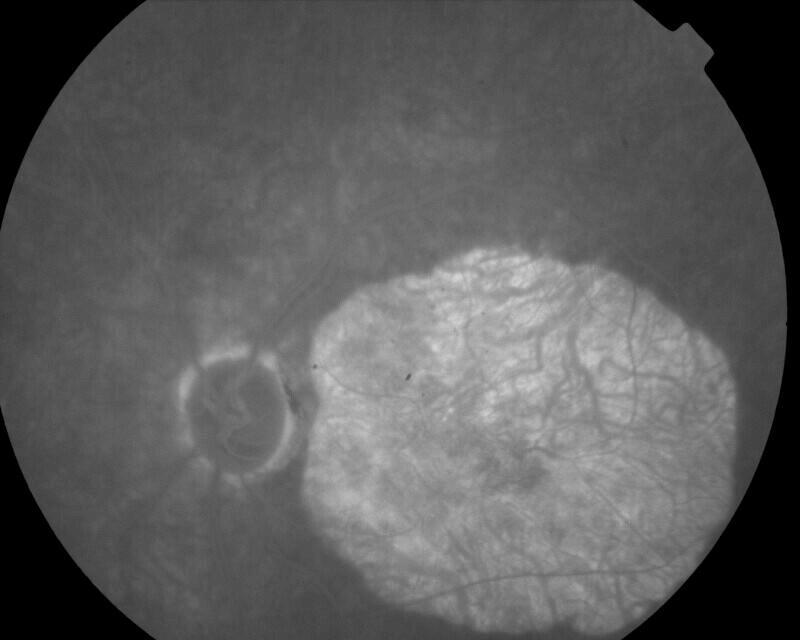

CICATRICE APRES EXERESE CHIRURGICALE DE NEOVAISSEAUX

IM000007.JPG